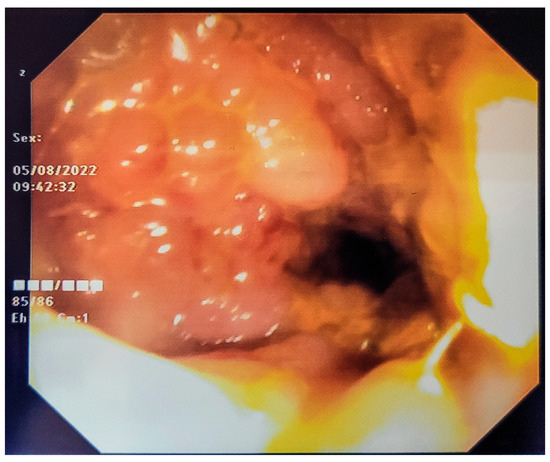

3. Detailed Case Description

| 25 | Present Case (2025) | 64/M | UCC G3/conventional and signet ring cell | GATA3, CK 20/CK5/6, P63, CDX | colonoscopy, rectal EUS TCB | rectal tenesmus, transit disorders (constipation/small volume diarrhea), moderate dysuria | DISTAL MEDIUM R |

| 25. | Present Case (2025) | 64/M | 0 | NO | Colostomy, NEOADJ CHT GC, RT | 15 M/D | T2N0M0 |